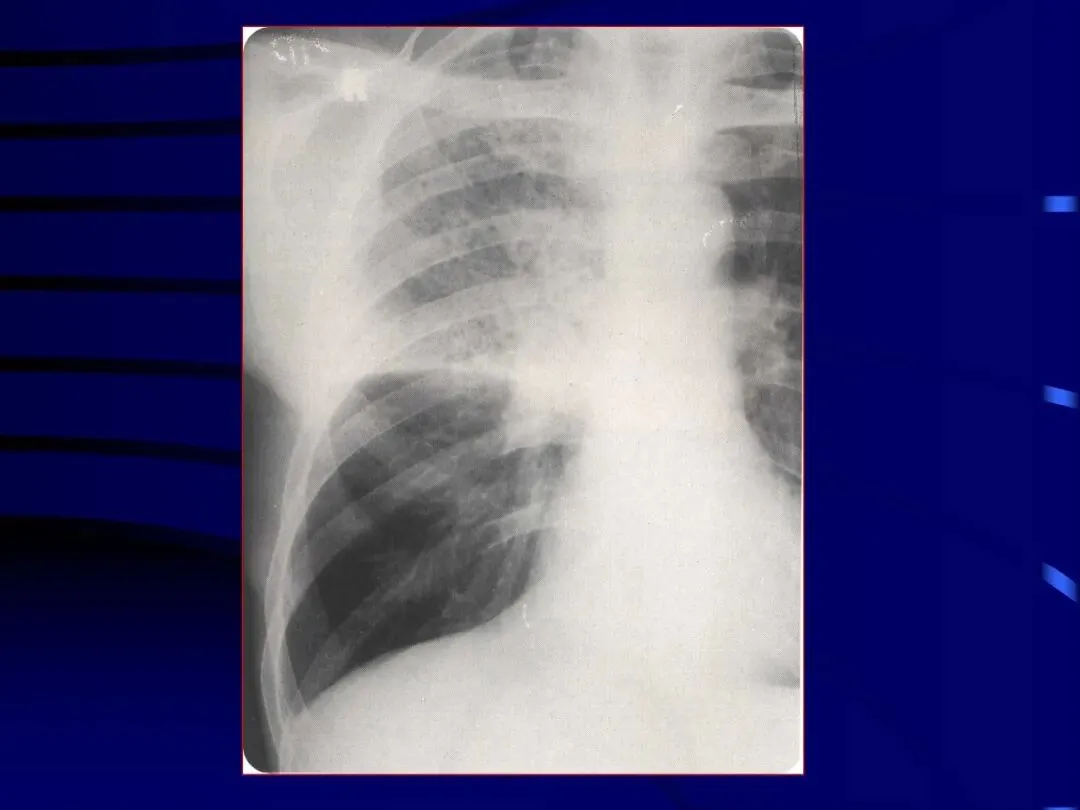

>内科学课件_肺部感染性疾病2-细菌性肺炎

内科学课件_肺部感染性疾病2-细菌性肺炎